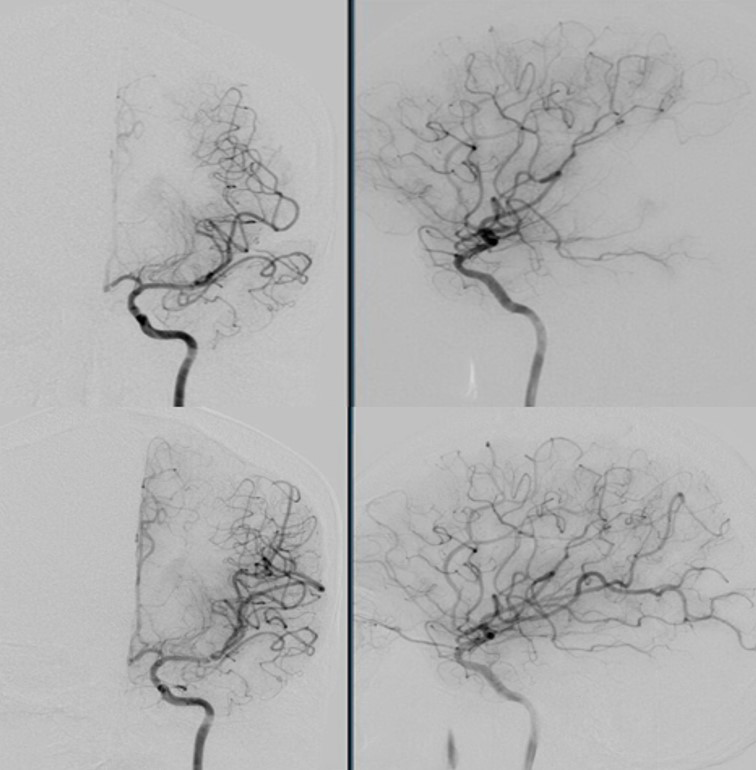

The patient was then taken urgently to the interventional radiology suite for mechanical thrombectomy of the left M2 thrombus. Using a 4mm x 15mm Solitaire stent-retriever TICI 3 flow was established after one pass (Figure 3). Thrombus on gross appearance appeared fibrinous. Microsopic evaluation of the thrombus showed a fibrin blood clot composed of multiple overlapping layers of fibrin admixed withplatelets, rare pools of red blood cells, and neutrophils, as can be seen in thrombus formed within 72 hours (Figure 4).

Figure 3 Cerebral angiogram in the AP and lateral views prior to mechanical thrombectomy with Solitaire stent-retriever system (top panel). Subsequent TICI 3 flow seen in the same territory following clot retrieval (bottom panel).